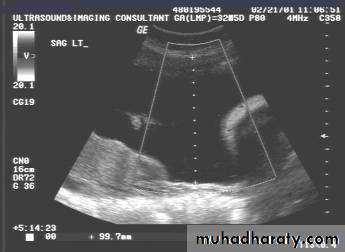

Ectopic pregnancy refers to the implantation of a fertilised ovum outside of the uterine cavity.

Radiographic features

Ultrasound

The ultrasound exam should be performed both transabdominally and transvaginally. The transabdominal component provides a wider overview of the abdomen, whereas a transvaginal scan is important for diagnostic sensitivity.

Positive sonographic findings include:

uterus

empty uterine cavity or no evidence of intrauterine pregnancy

Pseudo gestational sac or decidual cyst: may be seen in 10-20% of ectopic pregnancies

Direct visualization of the sac at the adenxia .